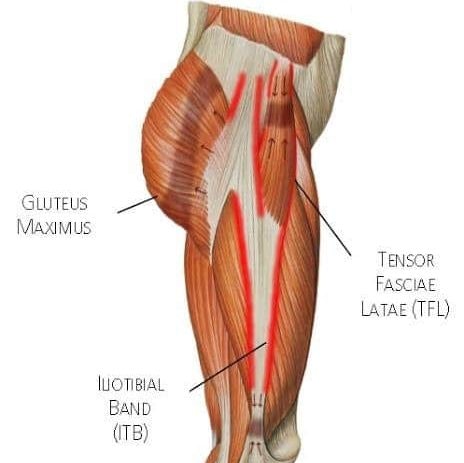

Iliotibial Band Syndrome (ITBS) is a common overuse injury in which symptoms are felt on the lateral part of your knee, especially during repetitive physical activity. Your IT band is a thick piece of connective tissue formed by 2 muscles in your hip (your glute max and tensor fasciae latae) that travels down the outside of your thigh and attaches just below your knee. ITBS is an overuse syndrome in which excessive tension in your IT band causes your IT band to rub against your femur, which causes discomfort and pain. If you’re experiencing pain in that area that worsens with activity, as well as other symptoms, like snapping or cracking in that area, you may be experiencing ITBS.